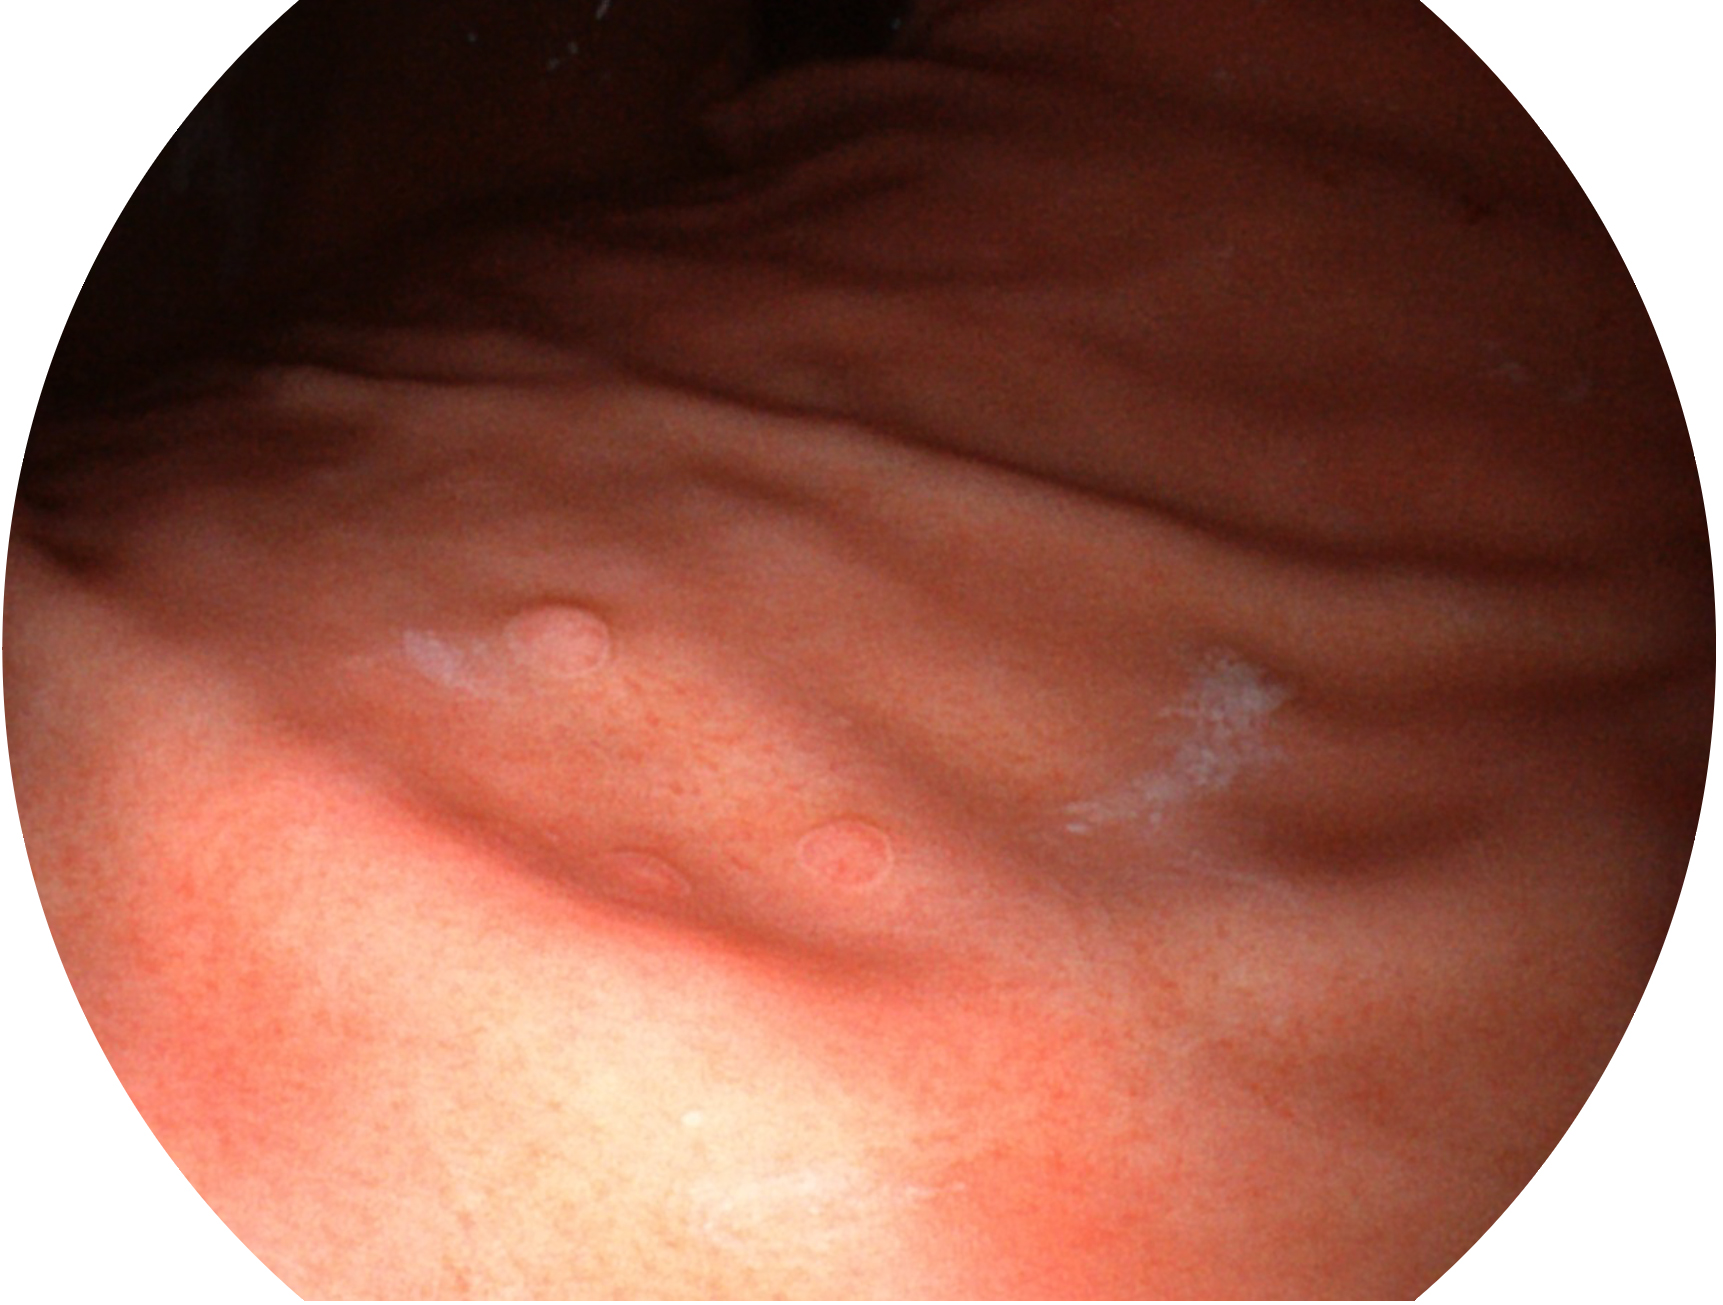

银河优越会新开发的内镜染色技术,主要是基于多波长LED 光源的开发,VLS-55Q 四波长LED 光源是由四个不同颜色的LED光按照相应照明模式所规定的特定发光比例进行合束后形成,合束后形成的照明光的光谱由红光、绿光、蓝光及蓝紫光这四个不同的波段范围构成。具有更高光谱自由度,通过光谱比例的控制,实现了聚谱成像技术,英文全称为“Spectral Focused Imaging, SFI”,缩写为“SFI”和光电复合染色成像技术,英文全称为“Versatile Intelligent Staining Technology, VIST”,缩写为“VIST”。